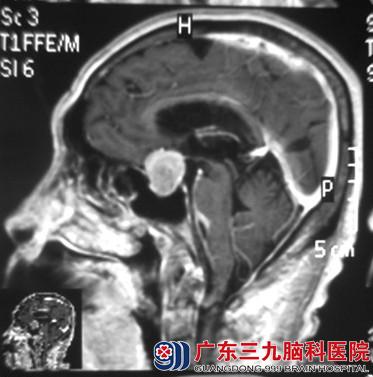

因视力进行性下降眼科求医无果,伴头晕加重,74岁高龄的吴大爷在儿孙的陪伴下来到广东三九脑科医院检查,行头颅CT检查提示:鞍区病变。进一步行头颅MR检查提示:1.鞍上区占位性病变,大小约2.8*2.0*2.0cm,明显挤压视交叉,考虑垂体大腺瘤, 2.幕上弥漫性脑萎缩;3.脑白质变性;4.脑MRA检查提示:脑动脉硬化;(以上2~4所见,综合考虑为老年性“皮层下动脉硬化性脑病”)。

术前